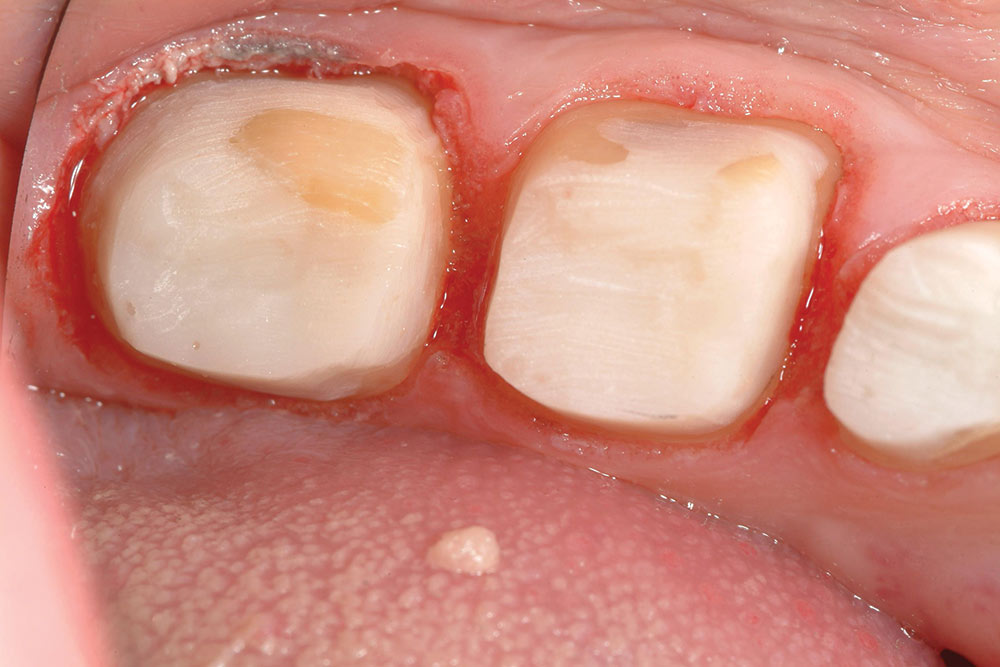

طول الطوق ferrule ومقاومته للكسر

أيهما افضل عمل سحب للسن بالتقويم او عمل استطالة للتاج؟

لابد من دراسة الحالة جيدا

وتحديد اي الخيارين هو الأفضل

بعض الحالات قد لايناسبها عمل استطالة للتاج crown lengthening

لانه قد يتسبب في تصميم للتاج بشكل سيئ جماليا وطبيا